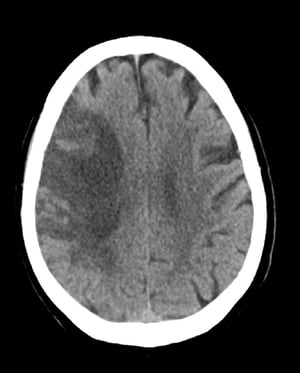

Підгострий інфаркт СМА (КТ)

This image shows low attenuation in the distribution of the right middle cerebral artery consistent with a subacute ischemic stroke with hemorrhage developing in areas of ischemia.

© 2017 Elliot K. Fishman, MD.